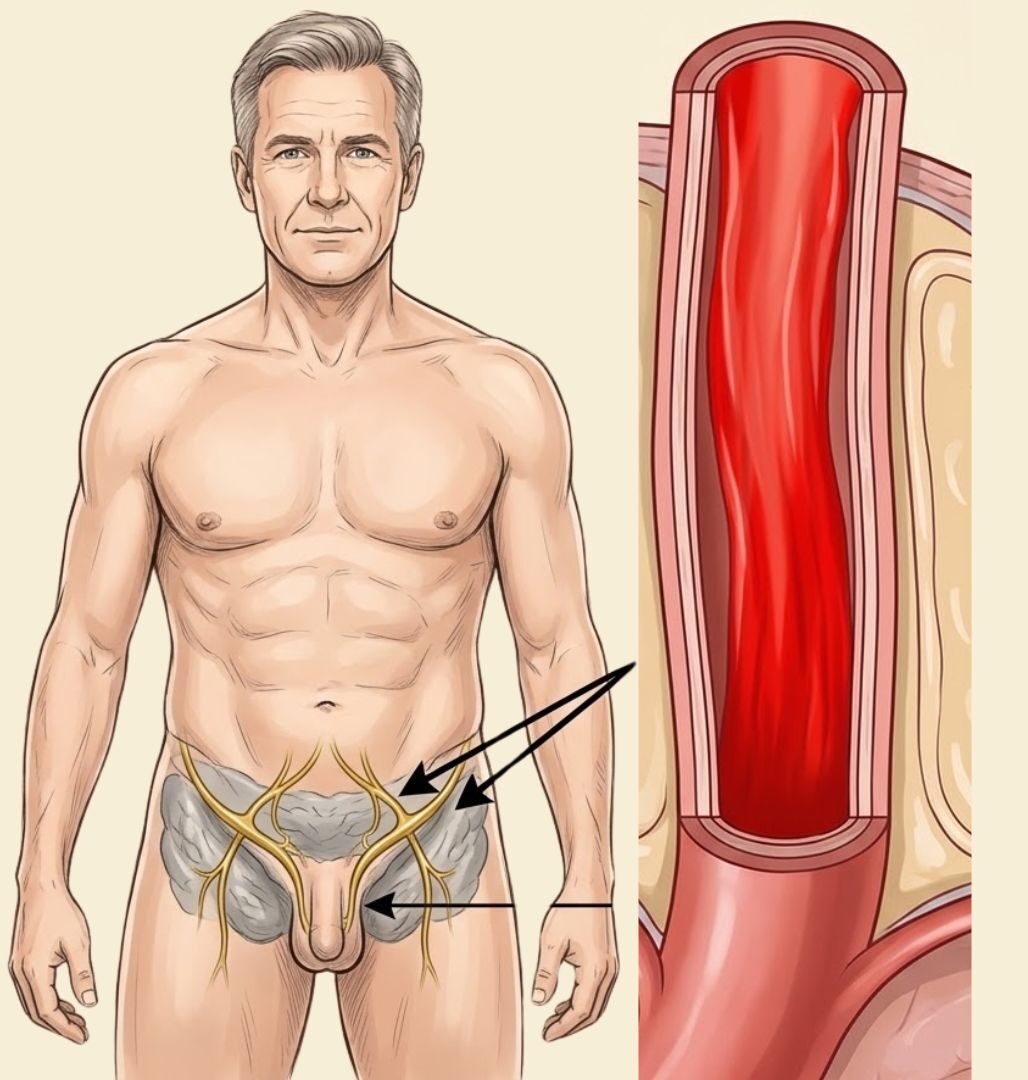

Deep inside your pelvis — wrapping around your prostate gland, threading along the base of your penis, and extending in a dense web of fibres all the way to the nerve endings at its tip — there is a network of nerves. Medical textbooks call it the cavernous nerve system. Think of it, for the purposes of this conversation, as the electrical wiring of your sexuality.

When you experience arousal — when your brain processes a touch, an image, a memory, a smell — it sends an electrical signal. That signal travels down your spinal cord, branches out through your pelvic nerves, and arrives at the cavernous nerve network. From there, the nerves release a chemical called nitric oxide. Nitric oxide causes the smooth muscle tissue inside the penis to relax. Blood floods in. The tissue expands. You have an erection.

That entire sequence — from the first flicker of arousal in your brain to a full erection — takes between eight and thirty seconds in a healthy man. It is as automatic as breathing. You don’t decide to have an erection any more than you decide to digest your food.

Now. Here is what happens when the wiring starts to fail.

The nerves in the cavernous network are coated in a protective layer called the myelin sheath.

This sheath does two things: it insulates the nerve fibre so the electrical signal doesn’t leak out, and it accelerates the signal so it arrives at its destination with full strength. Without an intact myelin sheath, the signal weakens. It slows. It gets lost before it reaches its target.

Over years — and this happens gradually, so gradually that most men don’t notice until the damage is done — the myelin sheath around the cavernous nerves begins to degrade.

The signals your brain sends become whispers instead of commands. The nerve endings stop releasing nitric oxide efficiently. The smooth muscle doesn’t relax. The blood doesn’t flood in.

This is not a failure of desire. This is not a psychological problem. This is not low testosterone, although testosterone decline can make the situation worse. This is a hardware failure — a degradation of the physical wiring that connects your brain’s arousal signals to the physical response in your penis.

The prostate gland sits immediately adjacent to the cavernous nerve bundle. It is, anatomically, neighbours with the wiring that controls your erections.